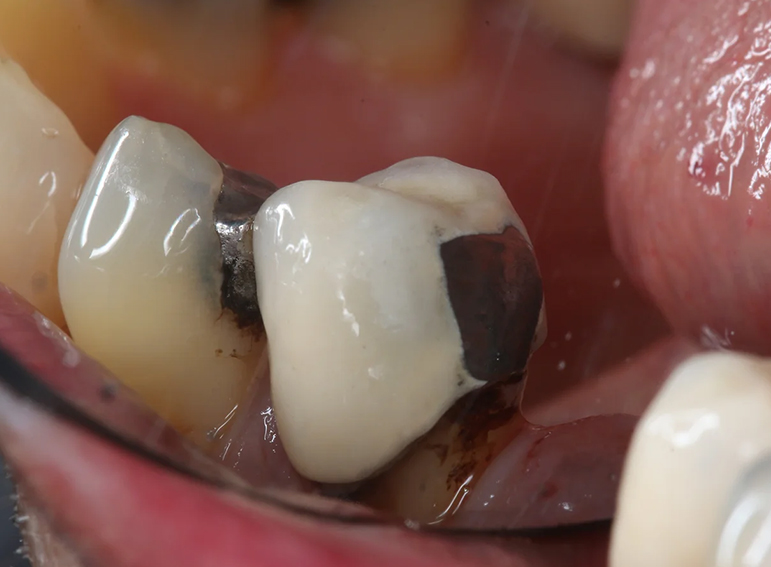

Case 18 – Prosthodontics

Extraction of failed bridge and temporary denture.